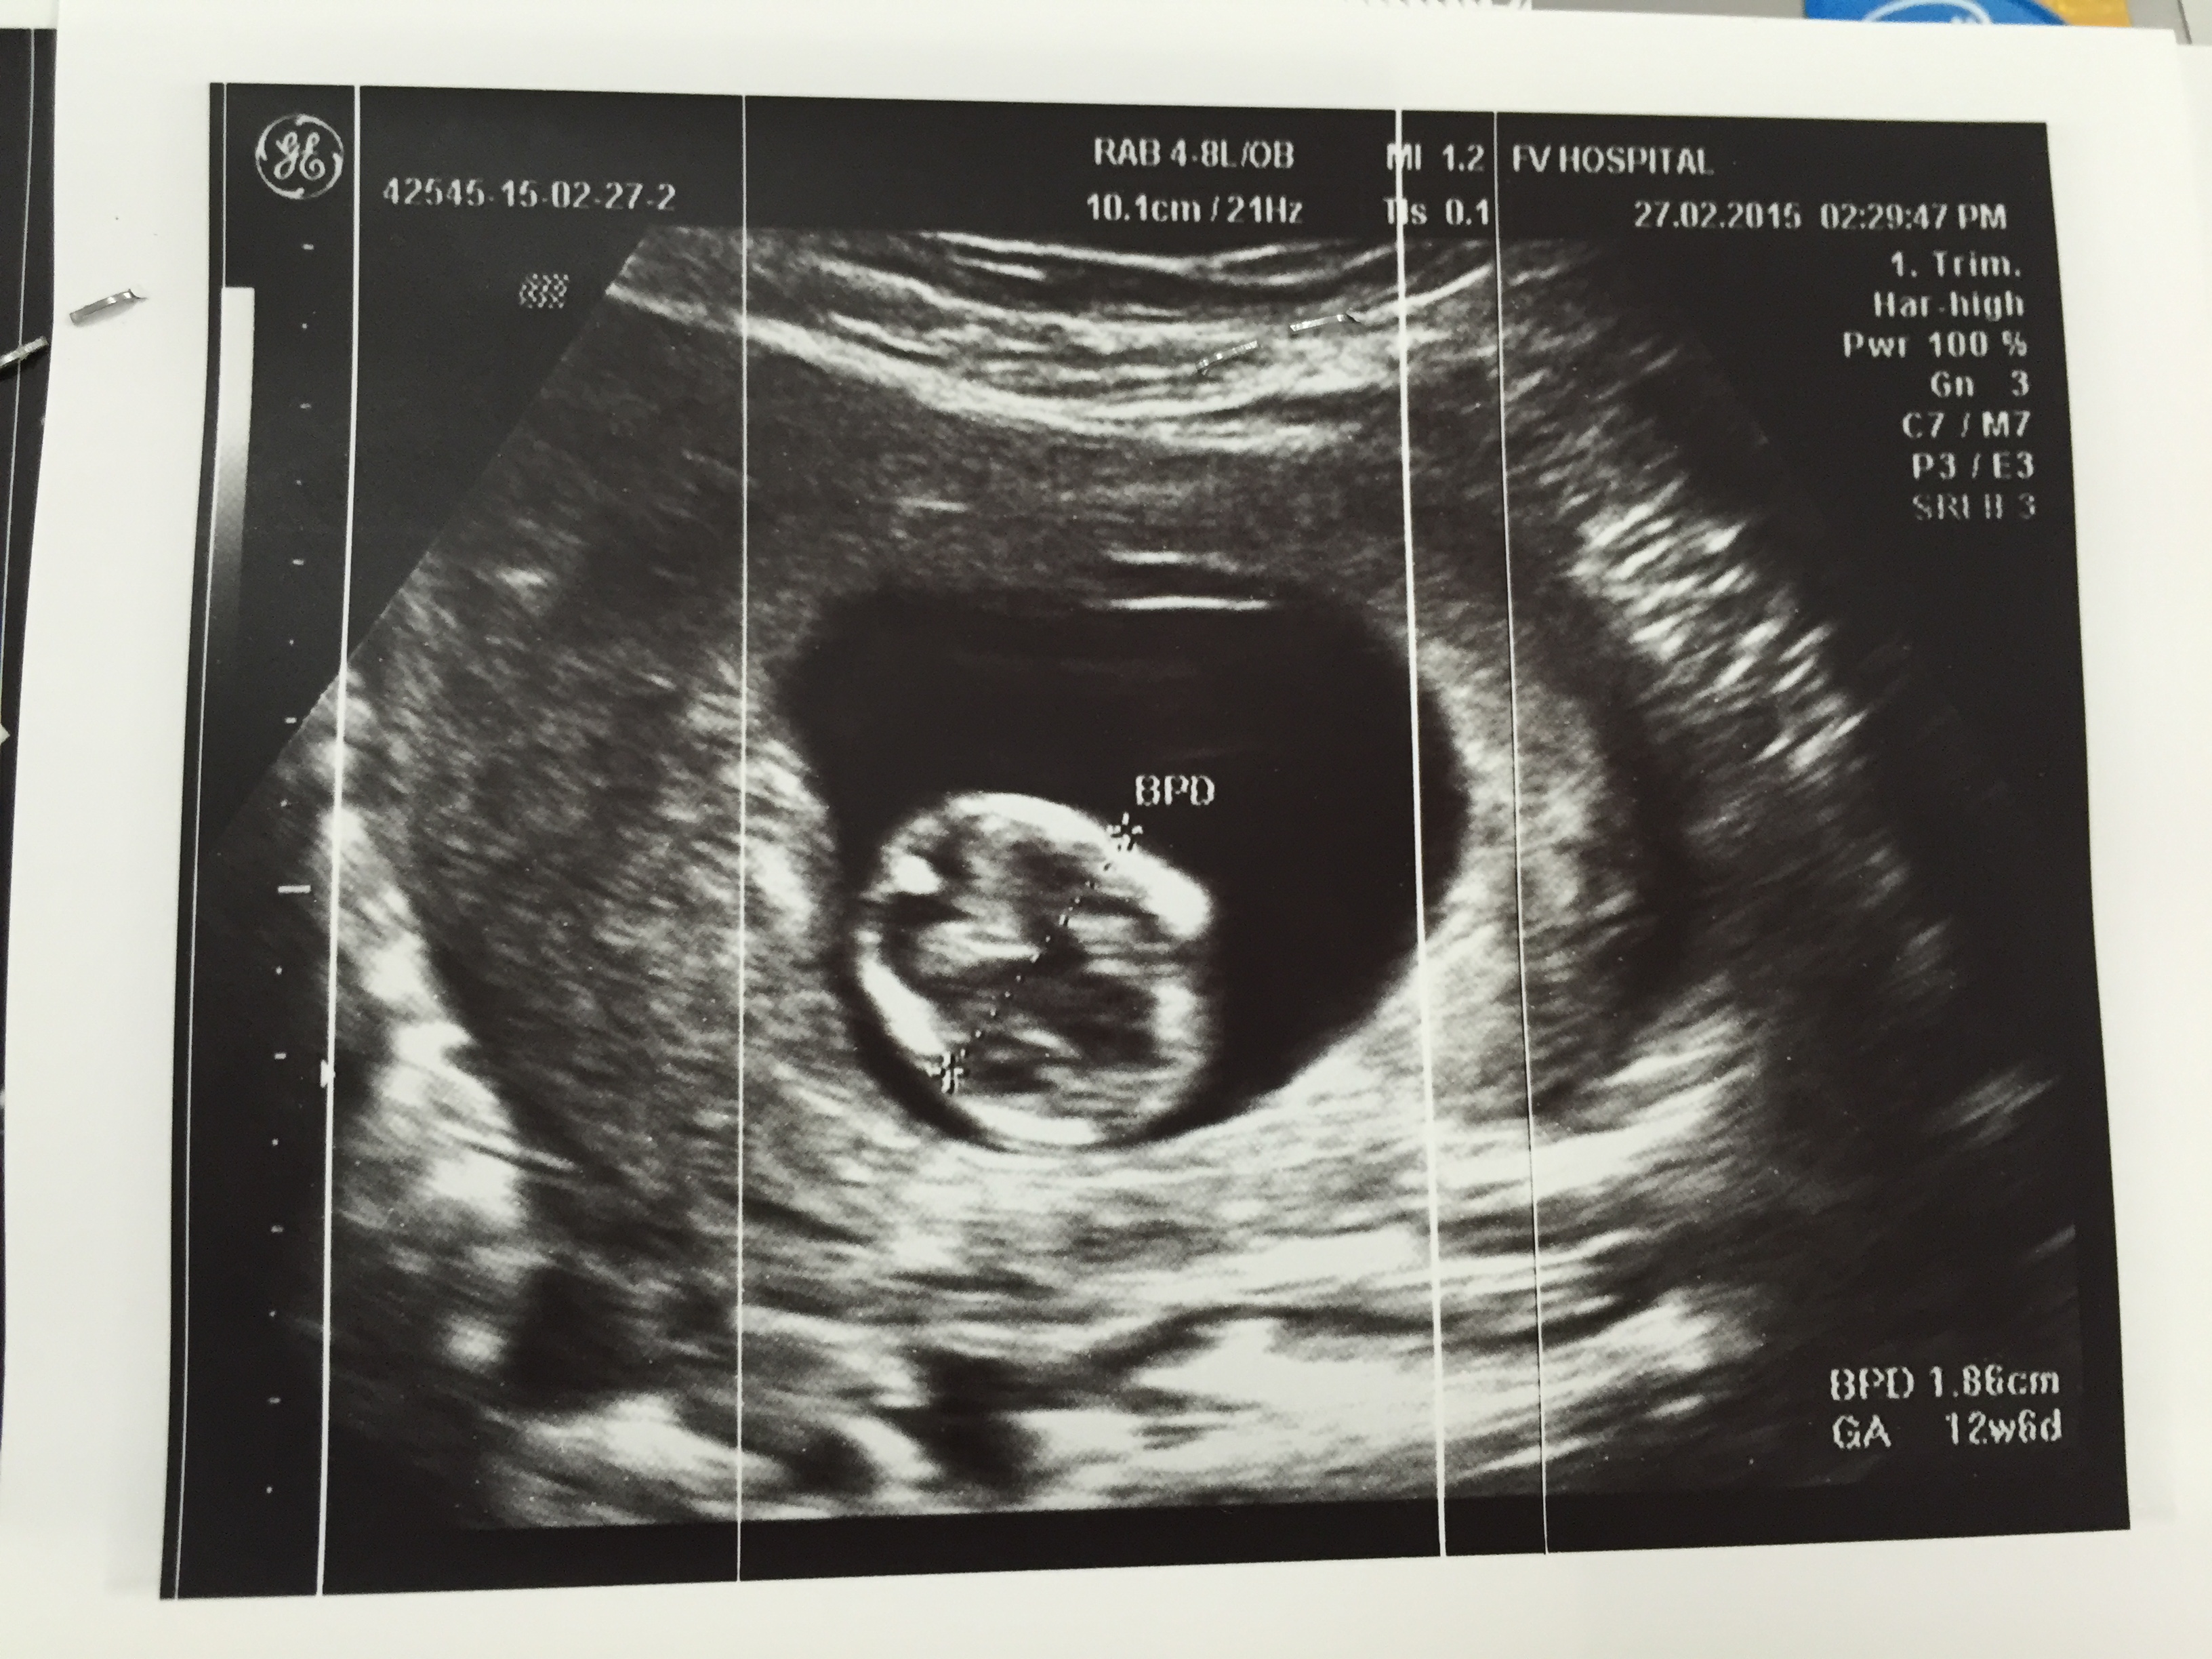

Attachment 24020

that is indeed the nub but its too high. It should be more where the bottom of your drawn circle is. baby was mid roll or lifting its bottom up and it caused it to be imaged wrong.so you are still at a 50/50.